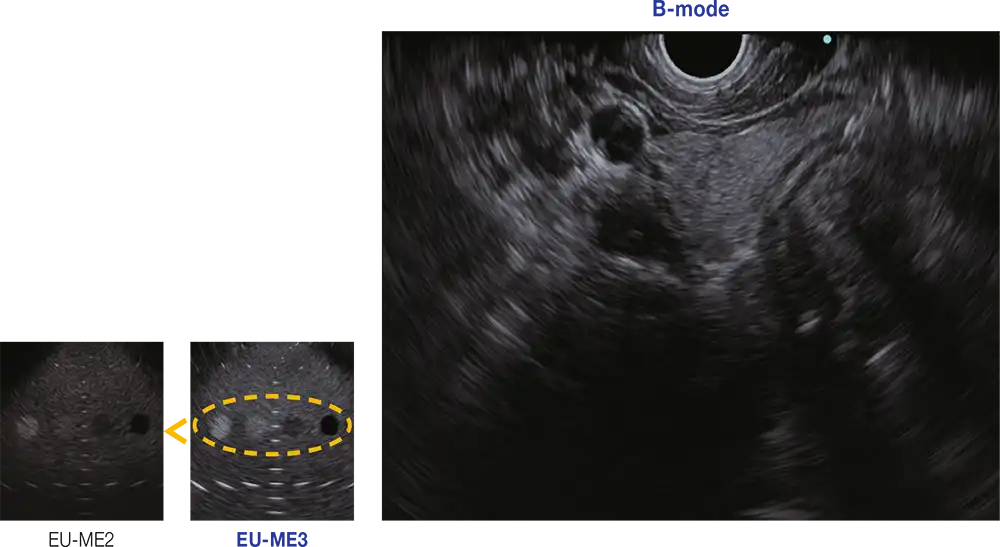

增强型B模式

EU-ME3 在一个紧凑的机身内提供了出色的图像质量和功能--与高端超声中心兼容。 与我们的传统处理器(EU-ME2)相比,B模式图像质量得到了大幅提升。